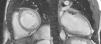

No nosso centro, optamos por seguir os critérios de Jenni por serem os mais frequentemente utilizados. Contudo, confrontamo-nos com a dificuldade em medir a espessura das camadas compactada e não compactada de forma rigorosa e reprodutível, o que, aliás, já tem sido demonstrado por diversos autores20,21. Por este motivo, todos os doentes foram submetidos a RMN para confirmação do diagnóstico. Esta técnica, além de ter demonstrado uma boa concordância com os achados ecocardiográficos, tem a vantagem de oferecer uma resolução espacial superior, permitindo uma melhor visualização do ápex e da parede lateral do VE, frequentemente envolvidos pela não compactação. Por este motivo, as imagens obtidas por RMN parecem-nos mais adequadas para avaliações quantitativas. Os critérios tradicionalmente aplicados são os propostos por Petersen, já referidos (ver métodos). Em 2010, Jacquier et al. demonstraram que a determinação do grau de trabeculação do VE, expresso como a massa da camada não compactada, pode ser utilizado no diagnóstico da NCIVE. Segundo estes autores, um valor de massa da camada trabeculada superior a 20% da massa global do VE é altamente sensível e específico para o diagnóstico de NCIVE22 (Figuras 1 e 2).

Outra vantagem da RMN é a identificação de focos de fibrose subendocárdica pelo realce tardio com gadolinium, o que pode ser útil na estratificação do risco arrítmico destes doentes. Na nossa série, apenas dois doentes apresentavam realce tardio na RMN, não tendo sido documentadas arritmias ventriculares malignas em nenhum deles.